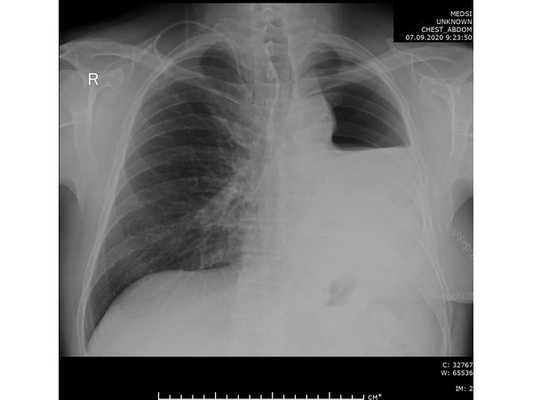

- рентгенографию легких в 2-х проекциях, линейную томографию, КТ легких;

КТ ОГК. Солидная мягкотканная опухоль в верхней доле левого легкого с морфологическими признаками злокачественности.

Диагностика злокачественных опухолей легких

Выраженные физикальные проявления на ранних этапах онкопроцесса в легких нехарактерны. Основным источником выявления злокачественных опухолей легких на стадии отсутствия клиники является рентгенография. Злокачественные опухоли легких могут быть случайно выявлены при проведении профилактической флюорографии. При рентгенографии легких определяются опухоли диаметром более 5-6 мм, участки сужения и неровностей контуров бронхов, ателектаза и инфильтрации. В сложных диагностических случаях дополнительно проводят МРТ или КТ легких.

- Лучевая диагностика. В обязательном порядке всем больным проводится двухпроекционная рентгенография легких. Рентгенпризнаки центрального рака легкого представлены наличием шаровидного узла в корне легкого и расширением его тени, ателектазом, обтурационной эмфиземой, усилением легочного рисунка в зоне корня. Линейная томография корня легкого помогает уточнить размер и локализацию опухоли. КТ легких информативно для оценки взаимоотношения опухоли с сосудами легких и структурами средостения.

КТ органов грудной клетки. Центральный рак правого легкого с полной обструкцией просвета правого верхнедолевого бронха